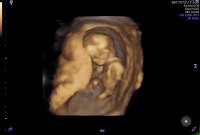

To søte små bamsemumser som vinket og sparka. Skulle ønske det gikk an å laste opp video, beveger seg mye!

Vanskelig å se tvilling en, for den ligger under tvilling to. begge er nøyaktig like store, 25 mm. Hodemål er 1 cm :D:love017:love017 9+0 i dag, men målt til 9+3.